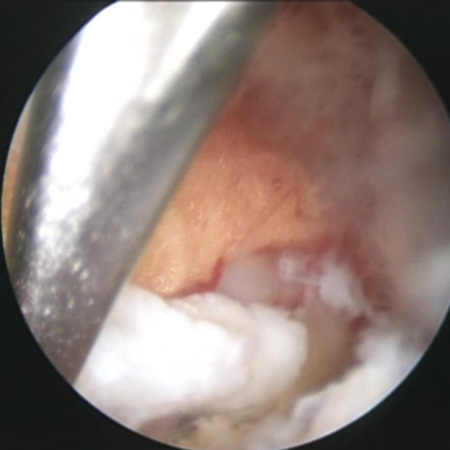

현재 표준 수술법은 요추 부위 근육을 약 30~40㎜ 절개하고 수술용 현미경으로 확인하면서 누출된 수핵을 제거하는 방식인 MD다. 과거 개방 수술법보다 회복이 빠르고 통증도 적지만 근육을 벌리는 과정에서 손상과 흉터, 그리고 통증이 불가피하다는 한계가 있다. 이후 보다 침습을 줄인 BED가 등장했는데 이는 요추 두 곳에 약 10~20㎜ 정도만을 절개하고 내시경 카메라로 병변을 들여다보며 수핵을 제거하는 수술법이다.